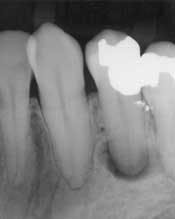

At first glance, the most obvious difference between the traditional patient exam and the digital new-patient exam is in the size of the radiographs. It is now possible to take a bitewing, a periapical film, or a panorex and show it on a large computer monitor that is visible to both the dentist and the patient (Fig. 1). With a laser pointer, it is possible to demonstrate normal or pathologic bone level, periapical pathology, tartar on teeth, the pulp chambers, and dental caries. Frequently, after just a few explanations, patients are able to detect other cavities, calculus, or areas of bone loss. When this happens, the level of ownership and responsibility taken by the patient increases significantly.

How does one use the digital radiographs, the digital photos, and the digital patient-education system effectively in the new-patient exam? The best way to illustrate this is with an example of a relatively simple, but frequent, scenario in which the exam can be used. A female patient in her mid-40s, with limited financial resources, has been seeing a dentist twice a year for as long as she can remember. The bitewing radiographs forwarded from a former dentist are unreadable copies that are more than one-year-old; no FMS or panorex are available. She presents with no chief complaints other than she has noticed that through the years her front teeth appear to be getting flatter and shorter. Besides this, the visit was for a routine teeth cleaning. The former dentist told her that flatter and shorter teeth were merely a part of growing older. In observing her smile, while reviewing her medical and dental history, it was obvious the patient was a chronic bruxer. When asked if she had been told that she might have gum disease, or whether she had ever ground her teeth, the patient responded that she had not. However, she did note that the dentist had performed a “deep cleaning,” and she had been encouraged to floss more regularly and visit the office more frequently for cleanings. Upon examination, it was observed that the patient had occlusal wear into the dentin on all upper and lower anterior teeth as well as many wear facets on posterior teeth. In addition, she had deep abfractions on upper bicuspids and two molars (No. 30 and No. 3), and had failed, large amalgams with recurrent decay and large fracture lines. She indicated that these two teeth occasionally were sensitive to chewing, especially with chips and pickles. Two- to three-millimeter recession was noted around several of the patient’s posterior teeth. Spot periodontal probing revealed pocket depths of four to six millimeters in both the upper and lower molar areas. The radiographs revealed calculus spurs on the molars, and lower anteriors with generalized two to three millimeters of bone loss evident. A large radiolucency also was visible around the root of No. 20.